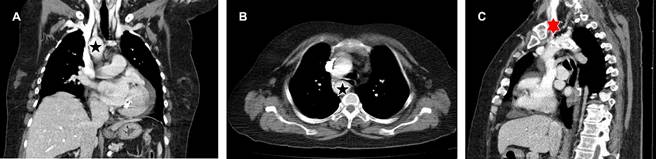

Paciente femenino de 64 años de edad a la que se le solicitó tomografía de tórax en alta resolución por parte del Servicio de Neumología debido a infecciones de vías respiratorias superiores recurrentes; sin embargo, como hallazgo, se visualizó arco aórtico derecho (Figura 1) con patrón de ramificación en espejo (arteria subclavia derecha y arteria carótida común derechos que se originan directamente del cayado aórtico y tronco braquiocefálico izquierdo) (Figura 2).

Figura 1: A) Imagen que muestra el arco aórtico derecho () en corte coronal, B) axial y C) arteria subclavia derecha en corte sagital () de angiotomografía de aorta en fase arterial.